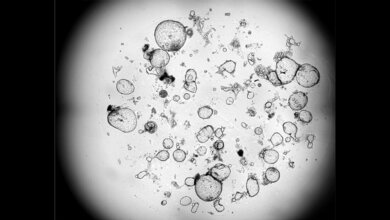

Doch auch bei der Diagnostik geht es mit Riesenschritten voran. Neben den neuen Möglichkeiten in der Bildgebung ist hier beispielsweise Liquid Biopsy ein Schlagwort. Die Nukleinsäureanalytik zum Nachweis von Tumorzellen und Tumor-DNA sorgt für Furore.